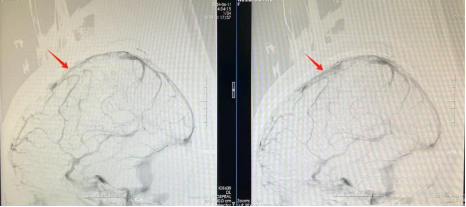

神经外十科及神经血管介入科急诊为患者行全脑血管造影。结果显示患者的上矢状窦、右侧横窦等颅内大静脉完全堵塞,证实是大静脉窦血栓。欧阳辉教授表示,虽然出血十分严重,但不能轻易开颅清除血块,应先对因治疗,疏通大血管(静脉窦)。否则患者的病情会持续恶化,危及生命。

随后,医生紧急将堵塞在患者静脉窦内的栓子取出,再应用抗凝血药物进一步稳定病情。“静脉血管通畅后,颅压下降,患者颅内的血块有望自行吸收,无需再行开颅手术。”神经外十科冯桂栗主治医师补充道。目前,小莫已恢复清醒,能够对话、吃饭,正在接受进一步康复治疗。

取栓前:静脉窦显影不佳(左);取栓后:静脉窦显影好转(右)